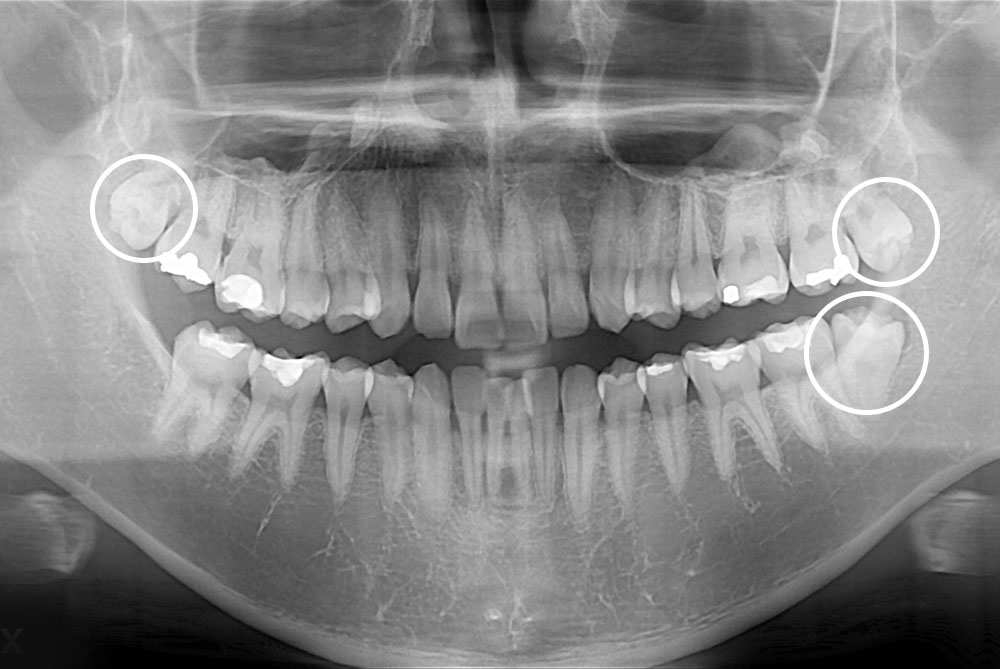

[사랑니] 매복 사랑니 발치

치료후 : 2021-05-24